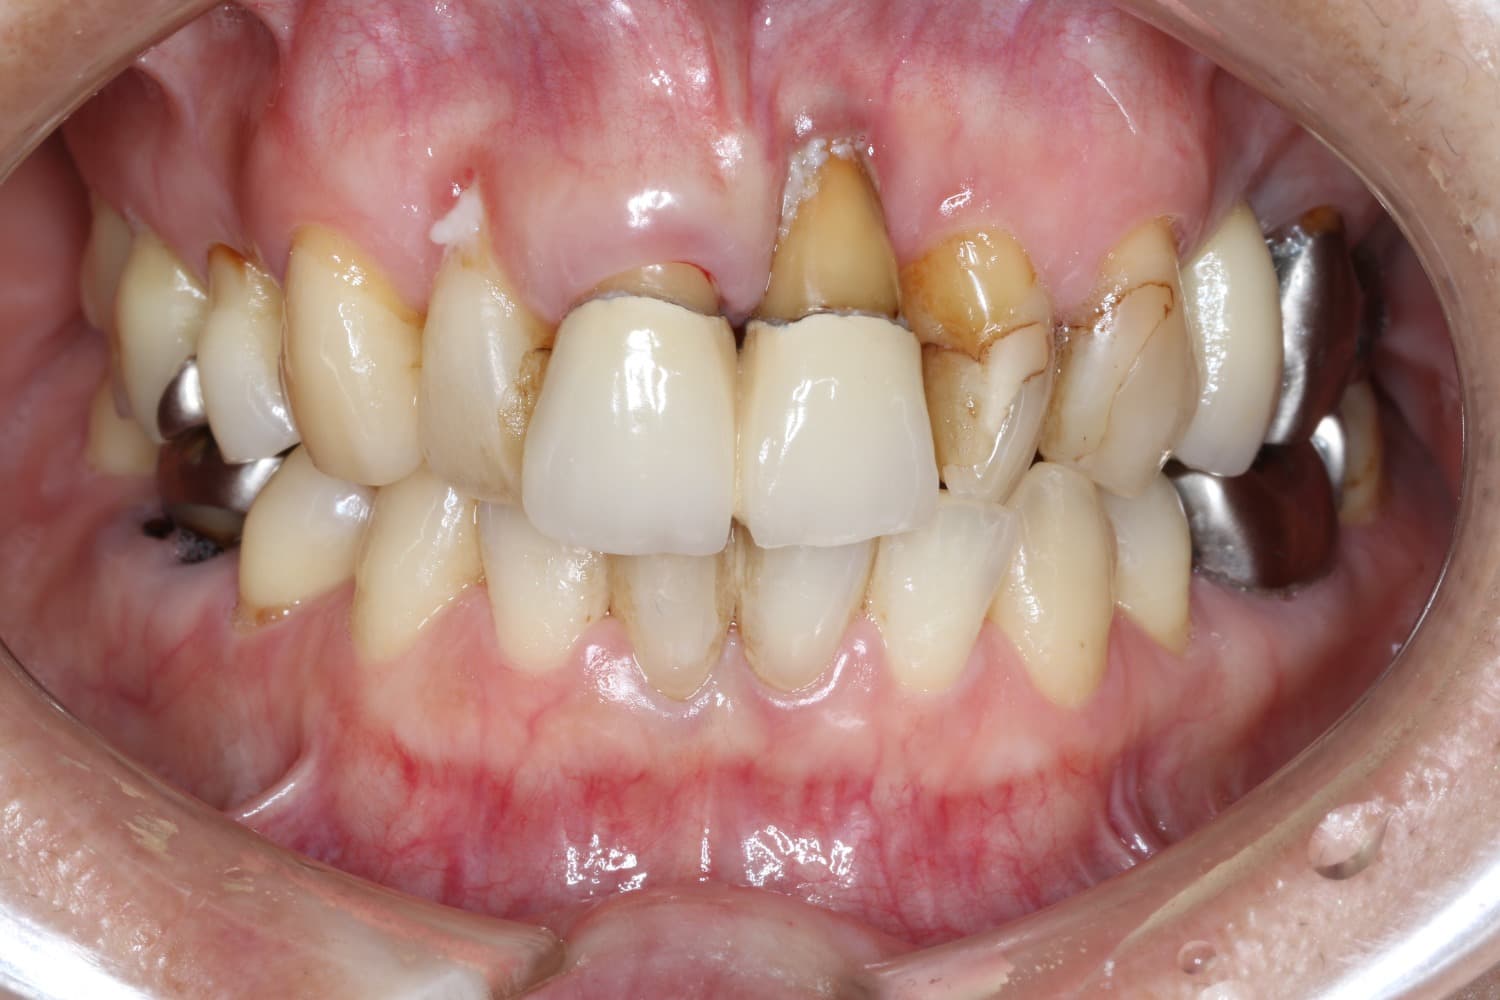

左上1のインプラント治療

Before

After

保存不可能な左上1を抜歯して、インプラント治療を行った 今回は歯間乳頭を作るために部分矯正も行う GBRやCTGも含む

年齢

30代

性別

女性

主訴

前歯が長くなってきた

治療期間

2年

治療回数

20回

費用

120万円

副作用・リスク

腫脹、疼痛